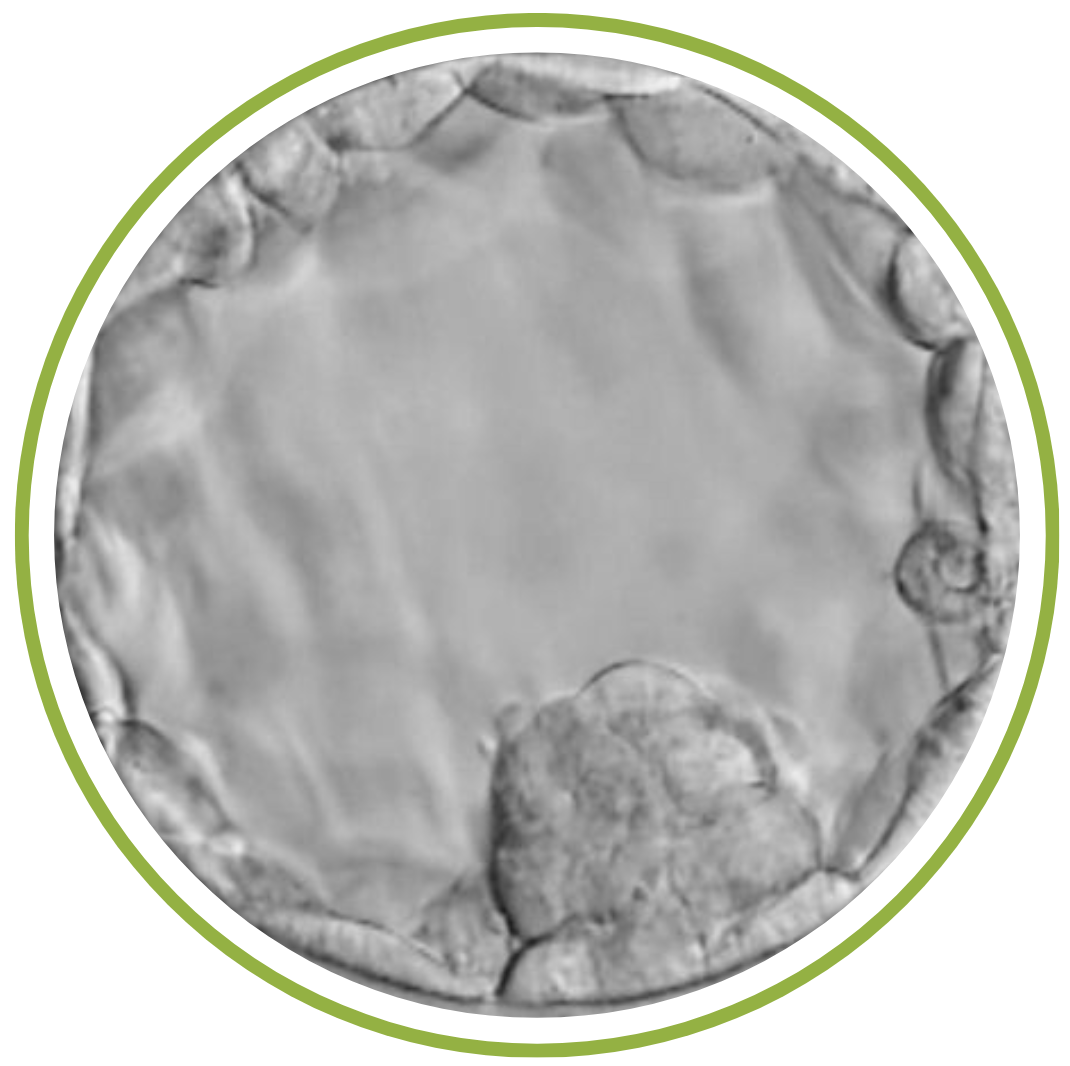

Nhiều trường hợp bệnh nhân khi nhận kết quả phôi tại Viện với ký hiệu phôi 4AA thắc mắc về ký hiệu này. Phôi AA là cách gọi để chỉ một phôi nang (phôi ngày 5 hoặc ngày 6) có chất lượng cao nhất theo hệ thống phân loại phôi phổ biến nhất (Hệ thống phân loại Gardner).

Dựa vào cách phân loại phôi nang theo hình thái, ký hiệu 4AA gồm có 3 yếu tố chính, được thể hiện bằng một chuỗi ký hiệu như: Số – Chữ cái thứ nhất – Chữ cái thứ hai.

- Số 4: Phôi nang đã giãn nở (làm mỏng màng ngoài).

- Số 5: Phôi đang nở.

- Số 6: Phôi đã nở hoàn toàn.

Chữ cái thứ nhất: (chất lượng khối tế bào bên trong – ICM)

Chữ cái đầu tiên đánh giá chất lượng của khối tế bào bên trong. Khối này sẽ phát triển thành em bé:

- A: Tốt nhất: Nhiều tế bào, tập trung chặt chẽ.

- B: Trung bình: Ít tế bào hơn, phân tán lỏng lẻo.

- C: Kém: Rất ít tế bào, thoái hóa.

Chữ cái thứ hai (chất lượng tế bào lá nuôi – TE)

Chữ cái thứ hai đánh giá chất lượng của tế bào lá nuôi. Lớp tế bào này sẽ phát triển thành nhau thai và màng ối:

Tốt nhất:

- A: Nhiều tế bào, dính chặt, đồng nhất.

- B: Trung bình: Ít tế bào hơn, kết nối lỏng lẻo.

- C: Kém: Tế bào lớn, thưa thớt, không đồng nhất.

Như vậy những thông tin trên đây đã cho ta biết ký hiệu phôi 4AA là gì. Đó là phôi nang loại tốt, một phôi nang có chất lượng tuyệt vời với tiềm năng làm tổ rất cao.